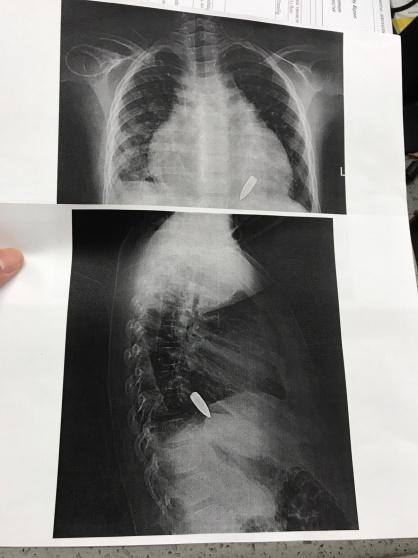

وفي عصر يوم الجمعة الموافق 22/3/2019 أصيب الطفل إبراهيم (8 سنوات) برصاصة في الكتف استقرت بالقرب من قلبه، ونقل على إثرها للمشفى الإندونيسي ومشفى الشفاء ولم يتمكن الأطباء هناك من إخراج الرصاصة لخطورة موقعها وعمره الصغير، لتبدأ إجراءات التحويل إلى مشفى المقاصد التي تأخرت بفعل إجراءات الاحتلال بضعة أيام أخرى.

وفور وصول الطفل إلى مشفى المقاصد يوم الاربعاء مع والدته، بدأ التحضير للعملية بعد إجراء كافة الفحوصات والصور اللازمة التي أظهرت وجود الرصاصة في مكان قريب جداً من القلب، ليتقرر بعد التشاور مع الدكتور فراس أبو عكر اختصاصي جراحة الصدر بدء العملية والبحث عن الرصاصة عن طريق المنظار الجراحي دون شق الصدر.

واستغرقت العملية التي أجراها البروفيسور نزار حجة مع طاقم متكامل ما يزيد عن 6 ساعات متواصلة، وفي هذا يقول الدكتور نزار: " كانت الرصاصة في مكان حساس، وكانت خطورة العملية تكمن في عدم إيذاء غشاء القلب وتفريغ السائل المتجمع حوله"، وأضاف:"بحثنا عن الرصاصة لمدة تزيد عن ساعتين حتى وجدناها وتمكنّا من إخراجها بنجاح".